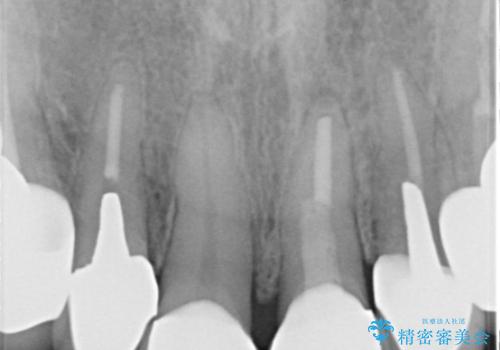

- 昔治療した前歯の色味が気になるとのことで来院されました。

昔に治療された前歯が変色しているのと、形態が自然ではありませんでした。

前歯2本をオールセラミックにすることにしました。